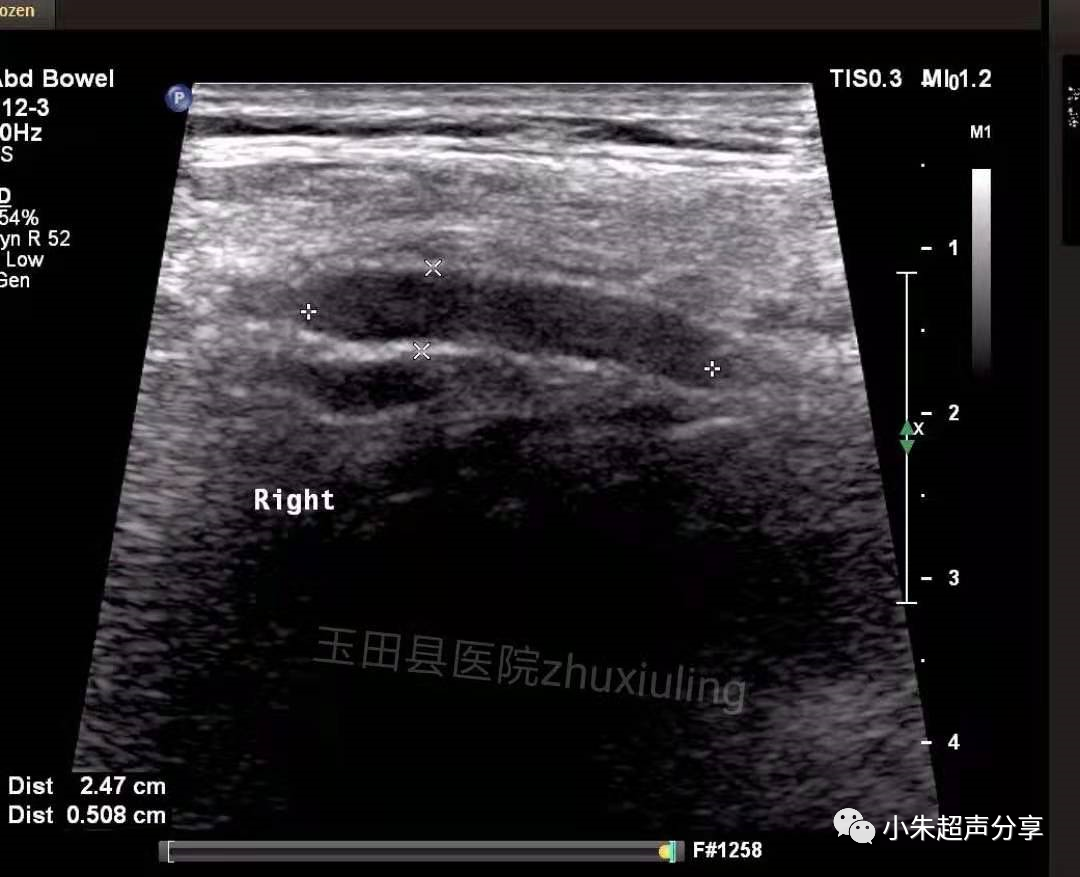

Case2:男,双侧腹股沟疝术后1月,双侧腹股沟区及阴囊疼痛,左侧为著。

超声检查时,置入的补片一般表现为条索样强回声,部分可伴弱声影,周围有积液时显示清晰,无积液衬托时常常显示欠清或难以显示。因补片类型及置入时间的不同,补片的形态亦会有所不同。

血清肿常表现为边界不清、形态不规则、透声差的无回声区,持续时间长者积液内可见多发分隔,无血流信号。在其内部或周边常可见到补片结构,病程长者,补片可卷曲变形呈波浪状(如Case2)。发现时应及时与手术医生沟通,必要时需多次穿刺抽吸,并需定期复查。Case1患者经抽液2次后好转出院(第1次抽出50ml淡红色液体,隔日抽出45ml淡黄色液体)。Case2患者经门诊保守治疗后痊愈。

该2例患者积液发生的部位亦有所不同,Case1患者积液位于右下腹腹腔内并与腹股沟区相通(考虑积液位置为原疝囊内),可能残留狭小缝隙,但未见腹腔内容物疝出;Case2患者积液局限于腹股沟区腹壁软组织内,未见与腹腔相通。